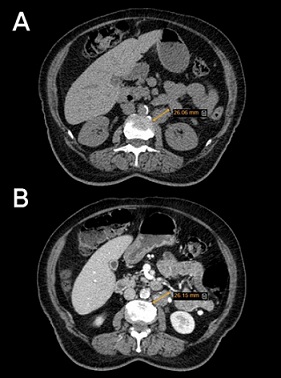

On the third day of hospitalization upper endoscopy was performed for investigation of the gastrointestinal tract malignancies. Biopsy showed chronic gastritis, mild chronic inflammation, and mild atrophy, without dysplasia or metaplasia, and Helicobacter pylori was not detected. Due to mild abdominal pain, abdominopelvic sonography and computed tomography (CT) were performed. Sonography of the pelvis revealed a large heterogeneous mass lesion (132 x 90 mm) posterior extending from the left adnexa into the right adnexa through the cul-de-sac, fluid in the interloop region particularly in the right iliac fossa, omental thickening in the left upper quadrant (LUQ) with a smooth pattern, and two nodules with hypoechoic centers and ill-defined borders. Infiltrative extension of the lesion with a heteroechoic mass (36 x 56 mm) was seen near the medial surface of the right ovary, but the major part of the right ovary was intact; therefore, the mass appeared to originate from the left ovary. Moreover, in the paraaortic region were seen some hypoechoic lymph nodes with a maximum short-axis diameter (SAD) equal to 19 mm in the inferior left renal artery pedicle. Abdominal and pelvic CT scan shown in Figure 1 and Figure 2.

Figure 2. Abdominal and Pelvic Computed Tomography Scan without (A) and with Contrast (B): two hypodense, ill-defined regions between the right diaphragm and posterosuperior segment of the right lobe of the liver, left paraaortic adenopathy under the renal pedicle 2.6 cm in diameter.